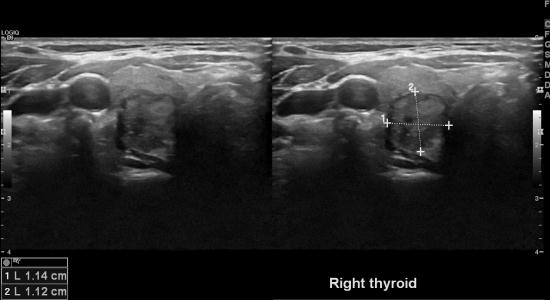

방암 진단후 PET scan 검사로 우연히 갑상선에

이상소견있어 본원에 의뢰되어

갑상선 우엽 유두암이 진단되신 분입니다.

유방암은 2기셨지만 갑상선 유두암은 크기가 1cm보다 약간

큰정도이며

임파절 전이소견이 없어보여

은 예후가 예상됩니다.